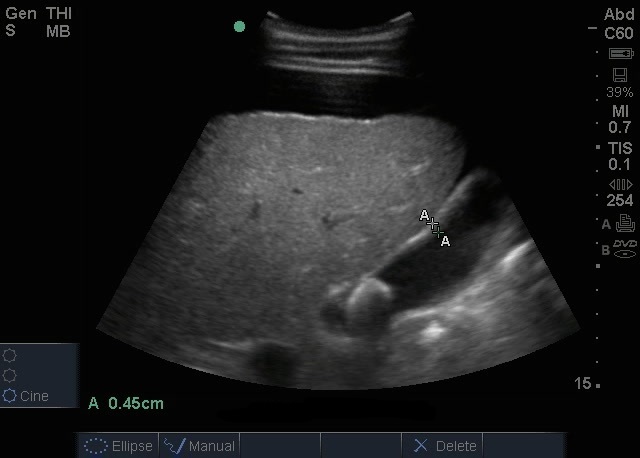

胆嚢石画像

腹水と胆嚢 (GB) 石